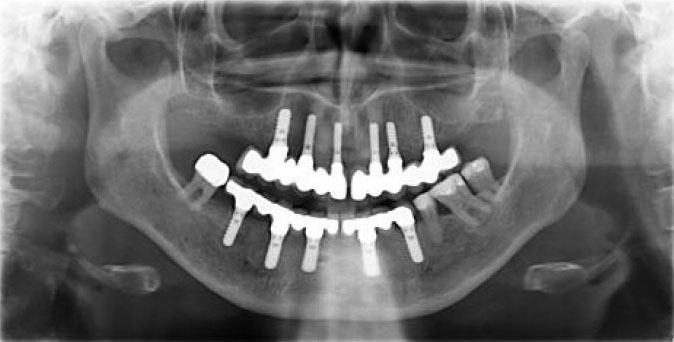

Nachher: Vollständig saniert und in Form und Funktion perfekt wiederhergestellt.

Patientin (geb. 1963) mit Parodontitis und zahlreichen defekten Zähnen im Ober- und Unterkiefer.

Nach Versorgung mit elf Straumann Implantaten (6 im Oberkiefer / 5 im Unterkiefer) und festsitzender Prothetik.